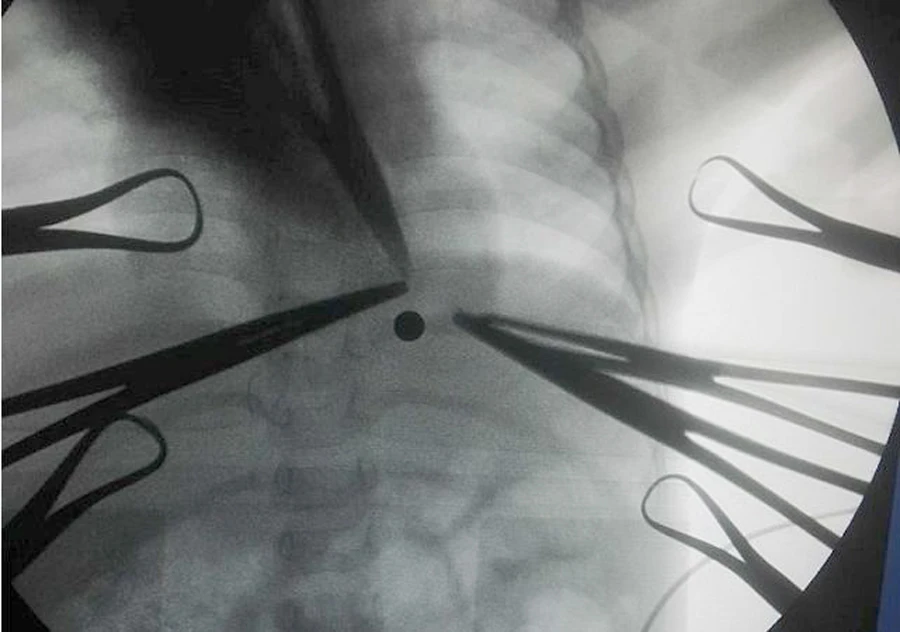

Hình ảnh chụp, chiếu cho thấy viên "đạn" bi xe đạp găm vào người bé T.

Trước đó, ngày 16-10, người thân đưa bé T. đến BV Sản nhi Nghệ An cấp cứu trong tình trạng có vết thương ở vùng ngực. BS Thái Văn Bình - Trưởng khoa Chấn thương chỉnh hình - Bỏng BV Sản nhi Nghệ An cho biết hình ảnh chụp chiếu tại bệnh viện cho thấy viên đạn hình tròn đi xuyên từ ngoài vào tận phía trong ngực bệnh nhi, gây rách màng phổi, tình trạng hết sức nguy hiểm.

"Sau khi hội chẩn liên khoa, các bác sĩ đã định vị viên đạn thông qua màn hình tăng sáng C-ARM, phát hiện dị vật cản quang và tiến hành phẫu thuật để lấy "viên đạn" ra ngoài. Đó là một viên bi xe đạp bằng sắt. Đây là phương pháp mới được ứng dụng tại BV Sản nhi Nghệ An" - BS Bình nói.